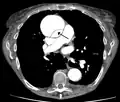

Computed tomography angiography is a fast, non-invasive test that gives an accurate three-dimensional view of the aorta. These images are produced by taking rapid, thin-cut slices of the chest and abdomen, and combining them in the computer to create cross-sectional slices. To delineate the aorta to the accuracy necessary to make the proper diagnosis, an iodinated contrast material is injected into a peripheral vein. Contrast is injected and the scan performed using a bolus tracking method. This type of scan is timed to injection to capture the contrast as it enters the aorta. The scan then follows the contrast as it flows through the vessel. It has a sensitivity of 96 to 100% and a specificity of 96 to 100%. Disadvantages include the need for iodinated contrast material and the inability to diagnose the site of the intimal tear.

-

CT with contrast demonstrating aneurysmal dilation and a dissection of the ascending aorta (type A Stanford) -

Chest CT with descending (type B Stanford) aortic dissection (red circle)

Type A dissection with pericardial effusion as a result.